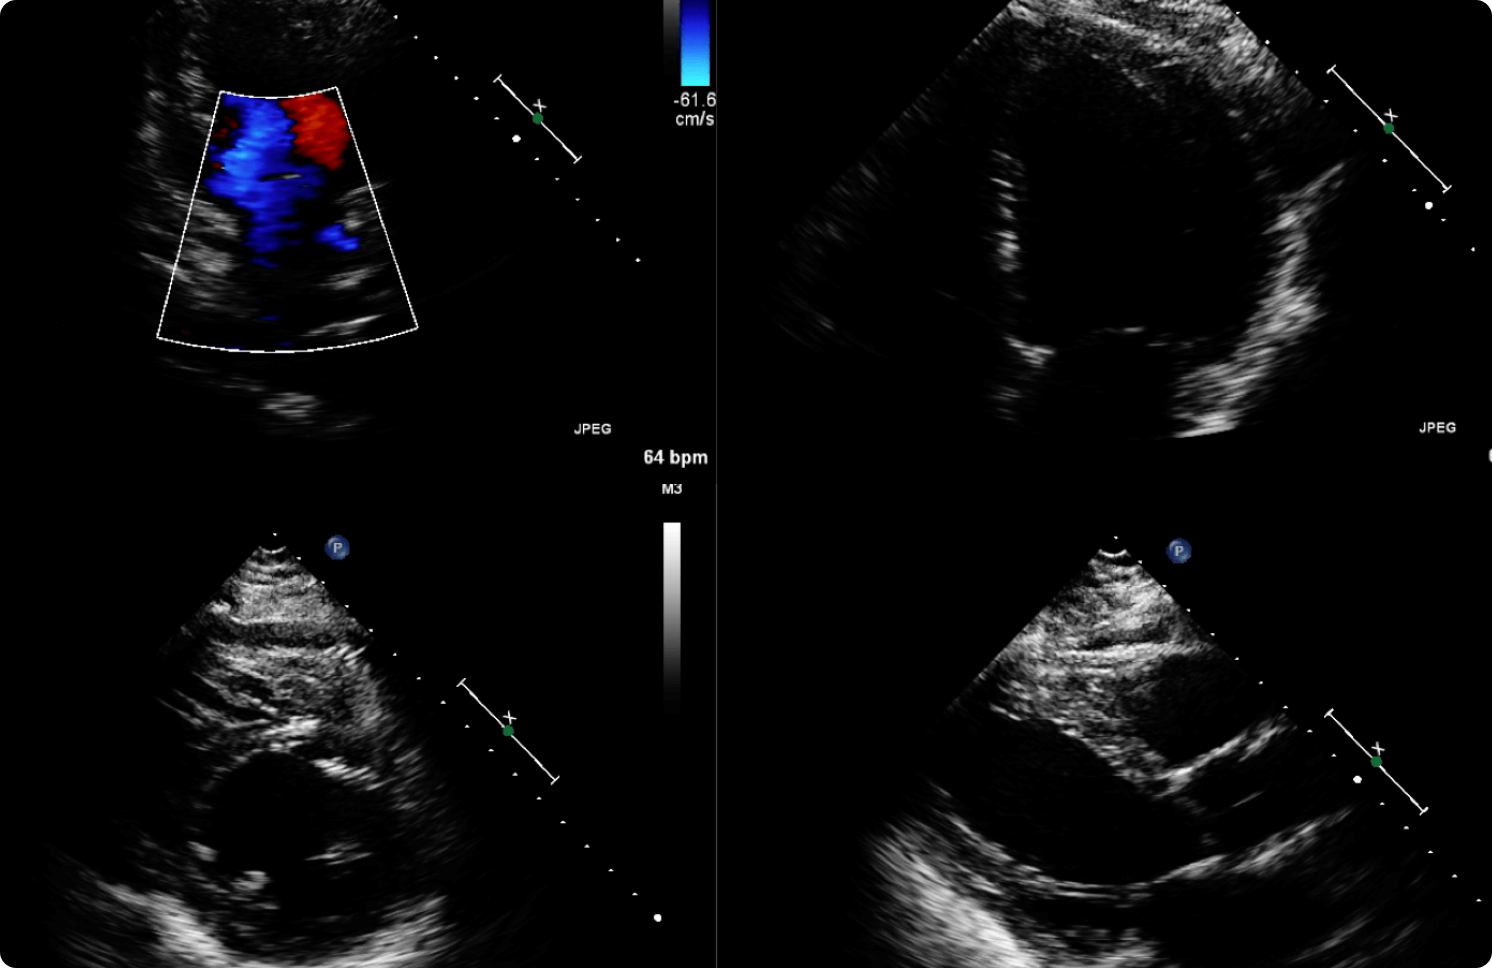

Echocardiography is an ultrasound examination of the heart which takes approximately 40 minutes to perform. Echocardiograms are safe and painless diagnostic procedures that use high-frequency sound waves to capture moving pictures.

Echocardiography may be ordered by your doctor for any of the following reasons: